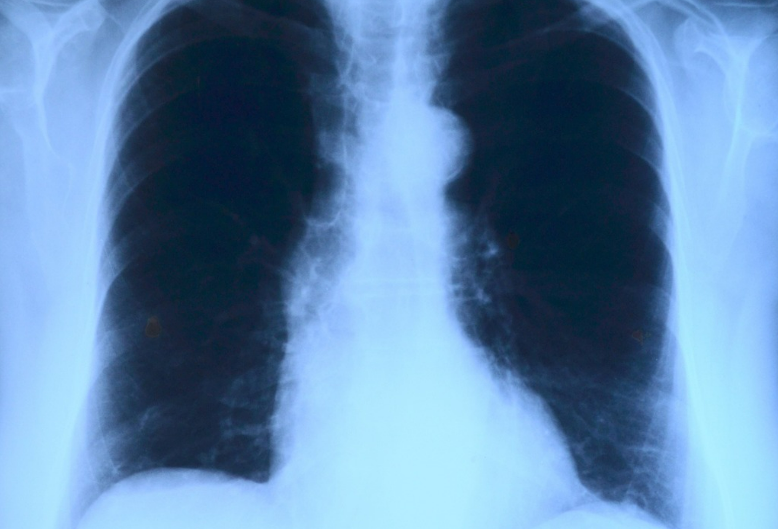

폐 질환

가운데 가슴 통증의 다른 가능성은 폐 질환입니다. 폐렴, 기관지염, 천식 등이 이에 해당될 수 있습니다. 이러한 질환은 가슴 중앙에서 호흡에 불편을 유발할 수 있습니다.

폐 질환으로 인한 통증은 숨쉬기에 문제가 있는 경우 더욱 뚜렷하게 나타날 수 있습니다. 폐 질환으로 인한 통증은 호흡곤란과 함께 발생할 수 있으므로 주의가 필요합니다.